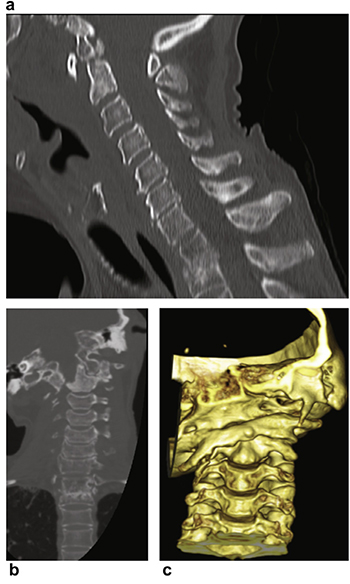

Sagittal CT scan (Fig. 2a) revealed increased atlanto-dental

interval, non-union of the odontoid fracture and kyphosis at T1/

T2 due to her previous fracture. Coronal CT scan revealed her right

occipital condyle resting on the C2/3 facet joint complex with a severe

lateral tilt and latero-listhesis secondary to erosion of the

right C1 and C2 lateral mass post-trauma. The left occipital condyle

was lodged in-between the left C1 lateral mass and the odontoid

process (Fig. 2b). Three-dimensional (3D) reconstruction (Fig. 2c)

demonstrated the severity of the cranio-cervical deformity.

Fig. 2. (a) Sagittal CT scan showing increased atlanto-dental interval, non-union of

the odontoid fracture and kyphosis at T1/T2; and (b) coronal CT scan showing

severe lateral tilt with the right occipital condyle resting on the C2/3 facet joint

complex and latero-listhesis secondary to erosion of the right C1 and C2 lateral

mass. The left occipital condyle rests in-between the C1 lateral mass and the

odontoid process. (c) Three-dimensional (3D) reconstruction of the CT scan showing

the severity of the cranio-cervical deformity. (This figure is available in colour at

www.sciencedirect.com).